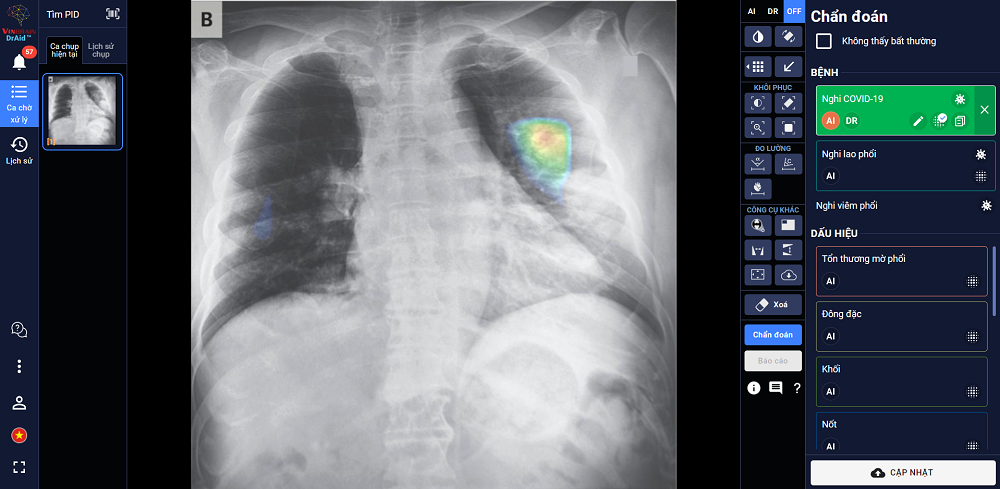

Một trong những ưu điểm của DrAid là hỗ trợ phát hiện và điều trị Covid-19 dựa trên ảnh X- quang ngực thẳng, gồm: Phát hiện nhanh để sàng lọc mầm bệnh trong cộng đồng, song song phương pháp xét nghiệm PCR - nâng cao độ chính xác, giảm thiểu tình trạng âm tính giả; Hỗ trợ đánh giá tiên lượng tình trạng bệnh nhân thông qua lịch sử hình ảnh chụp X-quang, từ đó có hướng điều trị phù hợp; Hỗ trợ tăng tính nhất quán và chuyển giao kiến thức của bác sĩ từ tuyến trung ương tới cơ sở.

DrAid chẩn đoán và tiên lượng điều trị bệnh nhân Covid-19 dựa trên hình ảnh X-quang ngực thẳng.

DrAid đượccác chuyên gia, nhà khoa học của VinBrain (công ty công nghệ thuộc Tập đoàn Vingroup) nghiên cứu phát triển. Phần mềm này có khả năng hỗ trợ chẩn đoán 20 dấu hiệu bất thường và bệnh lý về tim - phổi - xương trong vòng 5 giây, với độ chính xác trên 88%. Ngoài ra, DrAid chủ động đưa ra báo cáo y tế theo chuẩn quốc tế JCI, có khoanh vùng và đo kích thước tại khu vực cơ thể gặp vấn đề.